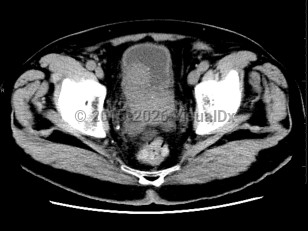

Prostate cancer

Most prostate cancers are identified at the local stage through annual screenings, and the majority of patients are asymptomatic at that stage. At later stages, physical findings may include perineal pain and urinary changes (eg, frequency, retention, nocturia). Urinary changes in men are more frequently the result of benign prostate conditions, which are sometimes found as comorbidities. Physical examination may reveal areas of induration, asymmetry, and/or prostate nodule. Diagnosis is confirmed via prostate biopsy.